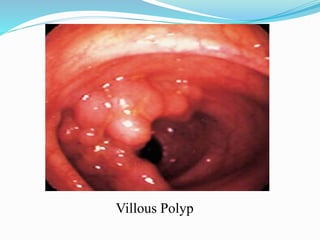

This document discusses colorectal polyps. It defines polyps and describes their types, including neoplastic and non-neoplastic polyps. It discusses adenomatous polyps in depth, noting their malignant potential increases with size over 1cm and villous architecture. Radiological diagnostic methods for polyps including single and double contrast barium enema and CT colonography are explained. The document provides an overview of polyp pathogenesis and genetic syndromes like FAP that increase cancer risk.